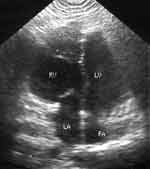

оси сердца влево, атриовентрикулярная блокада 2-й ст. типа Мобитц 1. При Эхо-КГ-исследовании

изображение, полученное из четырехкамерной позиции, позволило заподозрить инверсию

желудочков (Рис. 3). Используя метод дедуктивной эхокардиографии [2,3],

морфологически правый желудочек был нами идентифицирован по наличию модераторного

пучка, трабекулярности его верхушки, а также соответствующему ему трикуспидальному

клапану, который находился ближе к верхушке, чем митральный. В левое предсердие,

которое сообщалось через трикуспидальный клапан с анатомически правым желудочком,

впадали легочные вены. Правое предсердие через митральный клапан сообщалось

с анатомически левым желудочком. При этом при получении пятикамерной позиции

первой выявляемой магистральной артерией была легочная артерия, которая отходила

от анатомически левого желудочка. Это связано с тем, что легочная артерия при

данном пороке расположена больше кзади, чем обычно.

Рис. 3. При Эхо-КГ-исследовании изображение, полученное

из четырехкамерной позиции, позволило заподозрить инверсию желудочков.